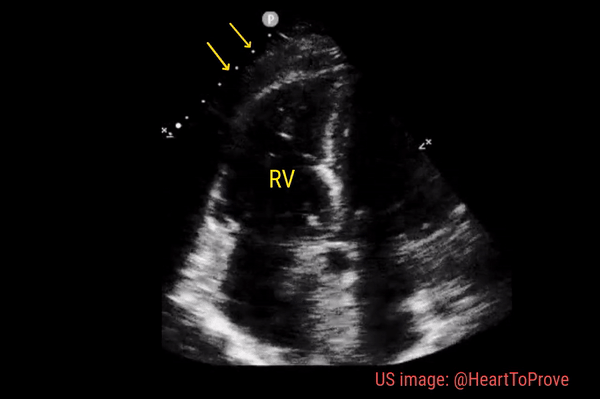

Dilated right ventricle

Normally, the right ventricle is triangular in shape with a cavity up to two-thirds of the left ventricle. Figure 3 demonstrates a case of severely dilated right ventricle (RV size more than that of LV) in a patient with severe pulmonary hypertension. If you obtain PSAX view in this patient, you will most likely see a D-shaped left ventricle due to flattening of the interventricular septum. We have to be very cautious in administering fluids to these patients because further increase in right ventricular size (due to fluid) coupled with obstruction to outflow (due to pulmonary hypertension) results in additional pressure on the septum leading to decrease in cardiac output and cardiogenic shock.